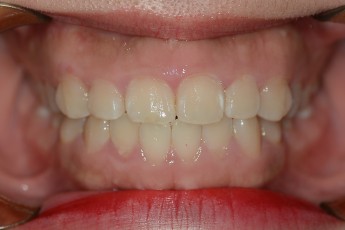

Before & After

- 덧니교정

After